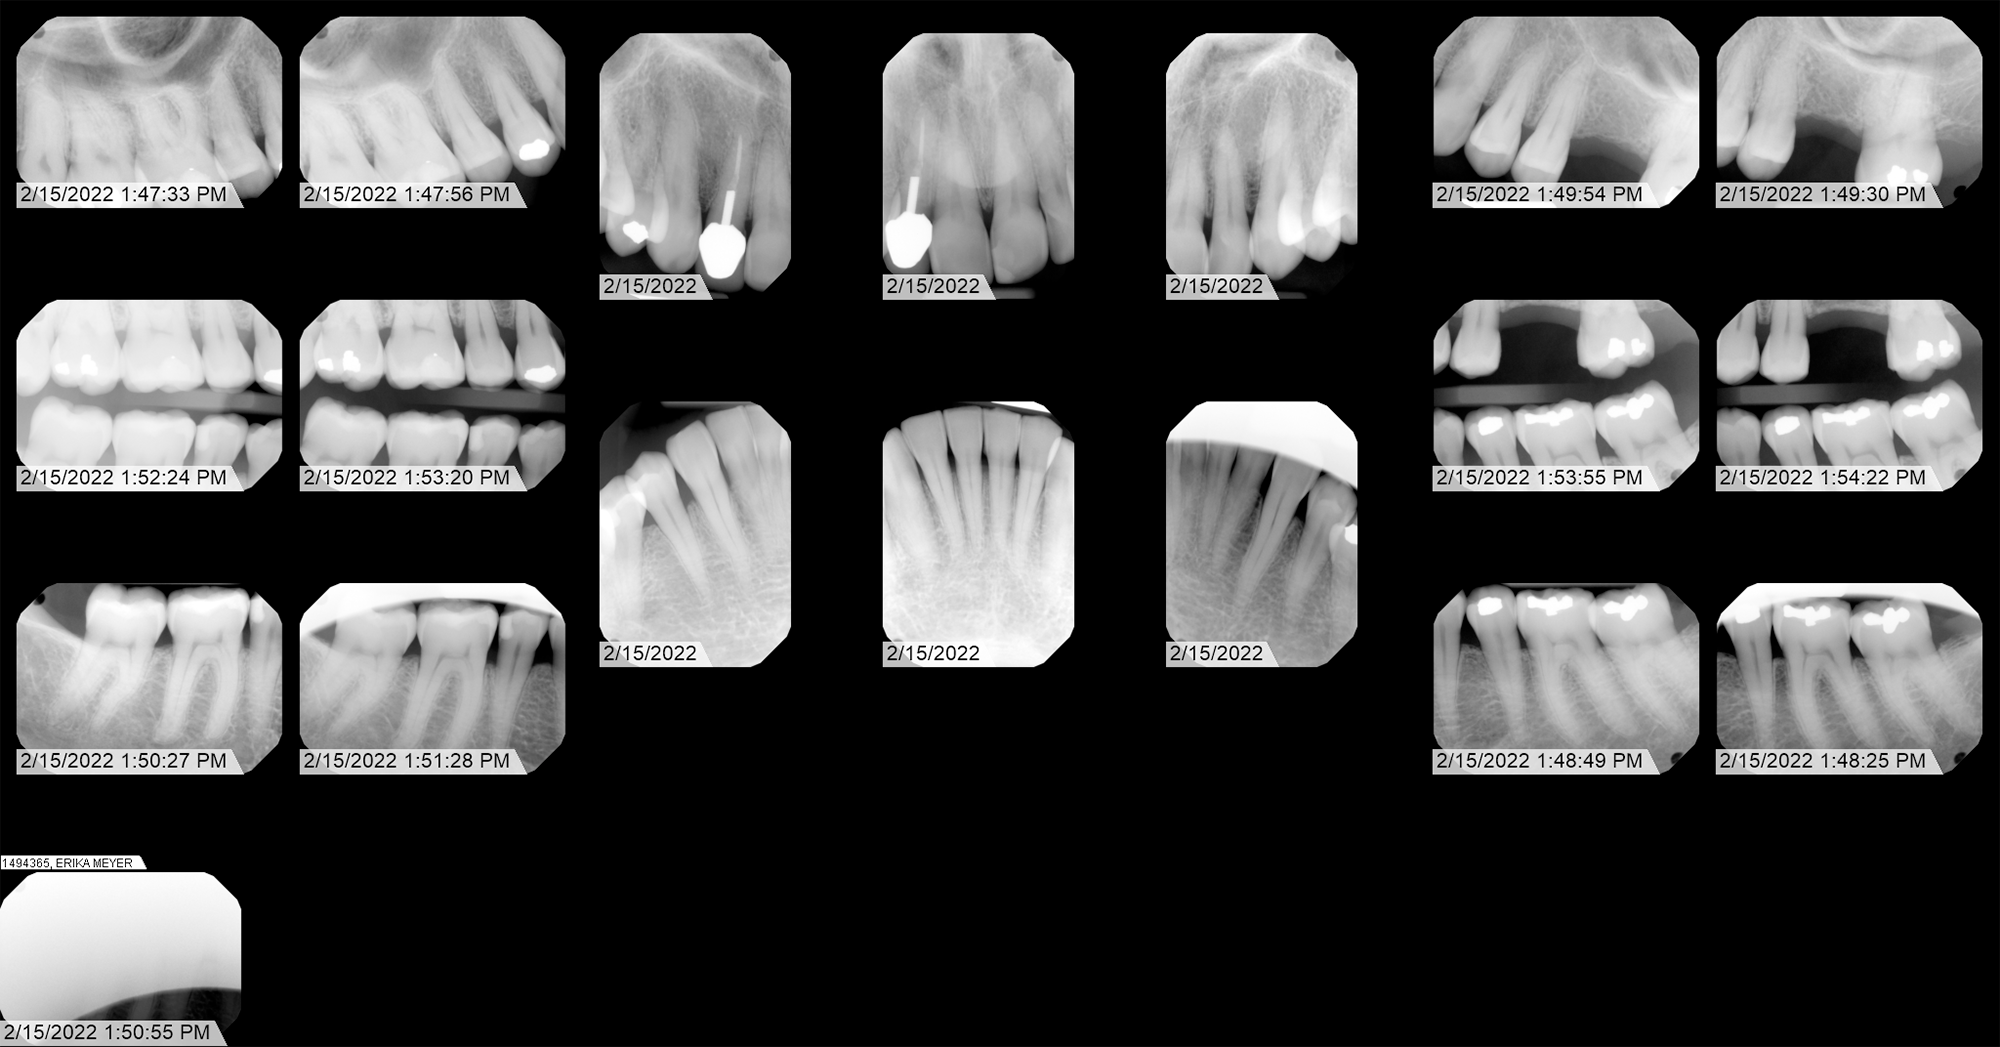

Radiographic Analysis (X-Ray)

Forensic identification of anomalous shape in extraction cavity.

| Capture Date | Feb 15, 2022 | 13:49:30 |

Case Narrative: Tooth 14 Anomaly

This investigation focuses on a localized, distinctly anomalous artifact identified in the jaw area, embedded in the jawbone over an extraction cavity (Tooth 14). The geometric angles and density of this finding suggest a non-biological origin.

The significance of this radiograph is further reinforced by a history of institutional resistance encountered during attempts at verification. Despite significant effort throughout 2022, I was unable to obtain original DICOM files from either Advantage Dental or Roots Dental. However, in 2026 I was able to locate and cite the federal and state laws requiring them to provide me with that information: HIPAA (45 CFR § 164.524) and Oregon Administrative Rule (OAR) 818-012-0030. As of this writing, Advantage Dental has provided me with those files, and to their credit, they did so quickly. I am still waiting for the single matching radiograph in DICOM format from Roots Dental, taken on April 8, 2022. Once I have that information, I'll create a page comparing the two.

Under the principles established by the 21st Century Cures Act and SWGDE forensic standards, original DICOM data is considered the "Primary Evidence." Prior to this year, these dentists insisted on substituting lower-resolution exports, effectively preventing the authentication of sensor-level metadata, a practice recognized in forensic circles as a barrier to independent verification.